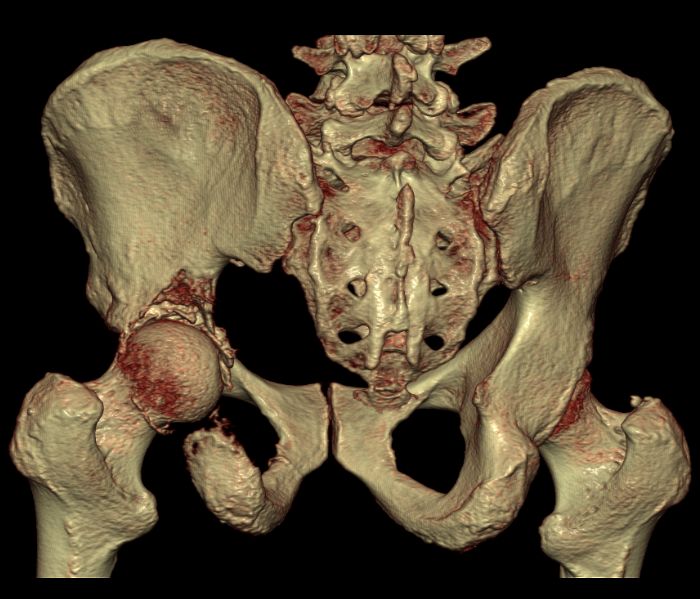

| Hüftpfanne | 74-jähriger Mann mit einem Adenokarzinom des rechten Lungenoberlappens pT1b pN2 Mo 1 Jahr nach Lobektomie Bestrahlung und

Chemotherapie. Die dorsalen Hüftpfannenteile links und Teile des Sitzbeins sind völlig zerstört.![]() |

Nach einem Sturz hat sich zusätzlich ein Haematom gebildet und der linke Hüftkopf hat sich nach dorsal verlagert.![]() |